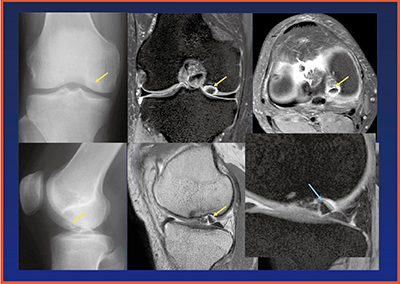

【症例2】離断性骨軟骨損傷

離断性骨軟骨損傷は,損傷状態によって保存療法か手術かの適応を決める。単純X線やMRIで診断するが,手術適応となる軟骨面の反転などは高分解能MR画像で観察可能となる(図9)。また,遊離体の有無や由来の確認にもMRIが有用である。手術では,はがれた骨軟骨片を生体吸収ピンで固定する治療が行われるが,術後評価にもMRIが用いられる。

図9 症例2:離断性骨軟骨損傷

離断骨軟骨片がunstable